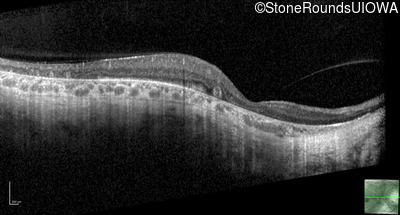

| Age at visit: 47 years |

| XL Choroideremia | CHM | Insertion of 212.3kb of Chr. 3 in intron 2 (IVS2+15,016 ins 212.3kb) | XL |